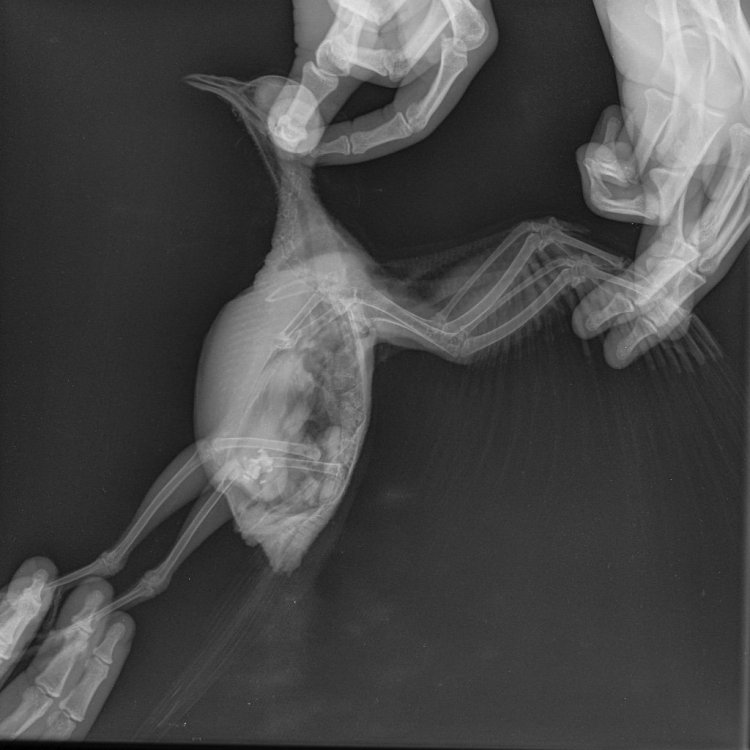

маленький принц Опубликовано 19 августа, 2024 #4 Опубликовано 19 августа, 2024 41 минуту назад, Viki. сказал: Очень худая, первый вариант чтобы не умерла от истощения СРОЧНО подкожные уколы глюкозы 5% с раствором Рингера или с физраствором 2 части глюкозы 5% и 1 часть раствора Рингера или физраствора на обычный шприц надень иглу от инсулинового шприца со съёмной иглой (бывает с несъёмной) оттяните кожу между лопаток и держа иглу инсулиновгого шприца параллельно спине так чтобы игла не могла войти ни в лёгкое ни в позвоночник введите иглу под кожу количество на глаз так чтобы не лопнула кожа ВНИМАНИЕ при любых манипуляциях с птицей голову держать ВЫШЕ зоба чтобы случайно не захлебнулся содержимым промежуток между уколами не менее 4 часов глюкозу нужно колоть каждый день пока более-менее не отъестся если нет глюкозы 5% а есть только глюкоза 40% нужно 11 частей физраствора и 1 часть глюкозы 40% это ~0.08 мл в глюкозы 40% и ~0.92 мл физраствора в инсулиновый шприц если нет глюкозы 5% а есть только глюкоза 10% нужно 2 части физраствора и 1 часть глюкозы 10% дополнительное место для подкожного укола глюкозы [quote]19.08.2021 в 05:13, voyagyur сказал: Если птица худенькая и слабая,можно добавить энергии инъекциями глюкозы 5 процентной 2 мл в смеси с р-ром Рингера или физрастворомд 1 мл.Греем в руках,выпускаем воздух иглой вверх и колем подкожно в складки кожи ... на сгибе крылышек,чтоб образовалась наполненная лекарством "пуговка". Больные и истощенные малыши плохо держат температуру тела,даже при комнатной температуре мёрзнут и теряют драгоценную энергию,ведь разница с их собственной температурой у воздуха почти в 2 раза. Кроме того при содержании с подогревом , быстрее идёт переваривание пищи . Можно коробочку с птицей ставить на кастрюлю с нагретой водой,укутанную в старые полотенца или покрывала,так температура может поддерживаться половину суток.Потом нагреваем снова Только проверить,чтоб дно коробки не было слишком горячим.Если горячо,простилаем картонку дополнительную или полотенце. Чтоб не мешала ручка,крышку накрываем в перевёрнутом виде,ручкой вниз Вы сразу заметите как оживился и повеселеет Ваш малыш в тепле. На фото,расположение складок кожи на крыле,для инъекции подкожной. [/quote][quote]Цитата(Марина_Л. @ 26 сентября 2011 @ 16:45) Сейчас следует взять себя в руки и сделать укол, сможете? Вам понадобится глюкоза 5% и раствор Рингера, укол делается в птичий пах, подкожно, за один раз я бы уколола 2 мл глюкозы+1 мл Рингера, можно в один шприц. Укол делается вдвоем. Например, колоть будет помощник. Тогда Вы берет птица в виде "букетика" или "бумажного кулька" (т.е. крылья плотно прижаты к телу, но не сдавливайте сильно, лапы вдоль туловища вытянуты). Затем одну лапку осторожно отводите в сторону (увидите нечто вроде птичьего паха ), зафиксируйте положение лапки. Теперь для помощника: в паху увидите тонкую кожную складку. Обрабатываете это место спиртом 70% и, выпустив пузырьки воздуха из шприца (фонтанчиком вверх; ВОЗДУХ ИЗ ШПРИЦА НЕ ДОЛЖЕН ПОПАСТЬ ПОД КОЖУ!), аккуратно прокалываете шприцом эту складку на глубину 5-7 мм (кожа в этом месте тонкая и полупрозрачная, увидите как далеко вошла иголка). Затем осторожно начинаете вводить раствор под кожу. При правильном введении кожа начнет надуваться в виде пузыря с жидкостью (не пугайтесь, это нормально). Потом можно аккуратно отпустить птицу отдыхать. В первые 15 минут птица может себя вести беспокойно, но это пройдет. Лучше всего брать пятикубовый шприц, но иголку с инсулинового однокубового шприца (того, на котором съемная игла) одевать. Цитата Цитата(Скалли) Я перевернула его на спину, чтобы колоть, но он вырвался, его всего скрутило, судорожно забился и умер. Я не знаю, как так вышло... и почему. Выходит, он прилетел за помощью, а я его добила. Цитата(dasha105) наросты пошли или слизь из зоба в дых горло- задохнулся Цитата(Zosia) Я колю подкожно на спине, в месте сведения крыльев, оттягивая кожу "шалашиком".В основание такого шалашика. И никакого переворачивания не требуется. Цитата(Ирина Алишад) Я не переворачиваю никогда. Кладу на бочок, лапку оттягиваю и колю в складочку. Если внутримышечно, то также на бочок, около киля перья раздвигаю и колю. примечание: глюкозу крепче 5% без Рингера или физраствора колоть НЕЛЬЗЯ! (риск некроза) глюкозу в 5% колоть без Рингера или физраствора можно (но лучше с ними)[/quote] про максимальное количество глюкозы в сутки: 42 минуты назад, Viki. сказал: Вы мне можете помочь его накормить? сварить кашку на воде без молока без соли и без сахара (рожь НЕЛЬЗЯ) и скатав из густой кашки шарики накормить ими накормив через три часа ощупайте зоб как найти зоб: ведите вдоль кости киля пальцем вперёд спереди между килем и шеей будет ямка а в ней мешочек = зоб если зоб опустел то накормите ещё если не опустел то напишите на форум сколько ещё осталось еды в зобу ВНИМАНИЕ до полного освобождения зоба НЕ кормить ВНИМАНИЕ кормить только при ПУСТОМ зобе (если накормить при не пустом зобе то есть риск что зоб остановится и птица рискует захлебнуться рвотой) так же через три часа после кормёжки сделайте фото помёта на белой бумаге при хорошем освещении для ориентировки взрослому в день нужно полторы-две столовые ложки сухого зерна с горкой (почтовому голубю который много летает в день нужно три столовые ложки с горкой) и это количество нужно считать до варки каши так как при варке зерно набухает и впитывает воду поищите в супермаркетах в отделах здорового питания или в веганских пшеницу или полбу (рожь НЕЛЬЗЯ) основа корма ~50-60% пшеница/полба а остальное смесь круп: гречка (лучше зелёная), мелкая чечевица, колотый горох, маш, овёс без кожуры (овёс в кожуре и хлопья НЕЛЬЗЯ) так же купите в аптеке недроблёные цельные семена/плоды растаропши и давайте как часть корма [b]бюджетный вариант корма:[/b] перловка в качестве основного корма (при условии если у птицы нет истощения) (если имеется истощение то перловка слишком низкокалорийная и нужно всё же пшеницу) чем кормить и что НЕЛЬЗЯ https://www.mybirds.ru/forums/topic/111964-sizarikinarodru/ как кормить если не ест сам https://www.mybirds.ru/forums/topic/34206-prinuditelnoe-kormlenie/ про голубят http://www.mybirds.ru/forums/index.php?showtopic=33566 как держать дома https://www.mybirds.ru/forums/topic/122247-golubi-tozhe-domashnie-pitomtsy/ когда начнёт летать чтобы не бился об стёкла познакомьте со окнами и зеркалами: поднесите к стеклу так чтобы коснулся грудью и клювом а затем дайте потрогать самому если на приёме у ветеринара случайно окажется коновал предлагающий усыпление на усыпление НЕ соглашайтесь (бывают коновалы которые сразу придумывают надуманные причины для платного усыпления) ВНИМАНИЕ при любых манипуляциях с птицей голову держать ВЫШЕ зоба чтобы случайно не захлебнулся содержимым (если же нужно например для рентгена уложить птицу на спину то зоб должен быть пуст для этого за три часа до переворачивания на спину НЕ кормить и НЕ поить) ВНИМАНИЕ при кровотечении греть НЕЛЬЗЯ ВНИМАНИЕ сушить или греть феном птиц НЕЛЬЗЯ птицы очень легко травятся запахами горячего пластика потому что их лёгкие способны дышать разряжённым воздухом на огромной высоте ВЫЖИТЬ и Здоровья Вашему голубёнку!

Viki. Опубликовано 23 августа, 2024 Автор #20 Опубликовано 23 августа, 2024 @маленький принц @маленький принц Этот тот же самый голубь, чем болеет не знаю, ранее писала что очень худенькая, кожа и кости. Уже несколько дней по вашим рекомендациям по 3 раза в день колим глюкозу с раствором 3 клюкозы 1,5 раствора. Вроде стала немного сама кушать. Вчера и сегодня один раз пришлось кормить через зонд по одному разу в день. Сегодня она после укола начала дрожать, по началу я думала что она замерзала, но дома очень тепло. помет то с водой , то более менее нормальный. Иногда бывает много белого пигмента в помете. Как ей помочь, почему она дрожит по утрам после укола? Глюкозу продолжаю колоть для поддержки организма. Но сегодня птичка особенно грустна, много спит и не хочет есть ( Как ей можно помочь ? Заказала кашу о которой Вы писали, завтра должна прийти и радостин, так же растопшу и пшеницу ждем завтра. До этого 5 дней пили таблетки Трихет, далее продавец советовала пропить Сальмовет, я их тоже купила, но пока думаю стоит ей их давать? Она и так слабенькая. Посоветуйте что нужно делать? Кормим горохом, зеленая гречка, маш, чечевица, добавляю немного зерносмесь она там любит черные семена выбирать+минеральная смесь в отдельной тарелке. Разбавила сегодня минералку Боржоми выпустив все газики с водой 50/50 но она пока к ней не подходила.

Viki. Опубликовано 2 сентября, 2024 Автор #37 Опубликовано 2 сентября, 2024 Все эти дни ездили по клиникам, сдавали анализы, общались с разными орнитологами, выяснилось что красавца больна хламедиозом…, плюс увеличение печени и воспаление жкт…. Каждый орнитолог расписывает свой курс лечения и дозировку, единственное в чем сходятся это в антибиотике тирозин 50, но дозы тоже разные… один док сказал что отек легких 15 процентов из ста что выживет, вторая сказала что не слышит хрипов, что нет отека но лечить надо. Сама по прежнему не есть, питаемся через зонд. Вес у нас 280 гр. В последнее время у нее бывает дрожь, один док сказал невралгия, а то что я начиталась в интернете вообще не хочу писать… 1